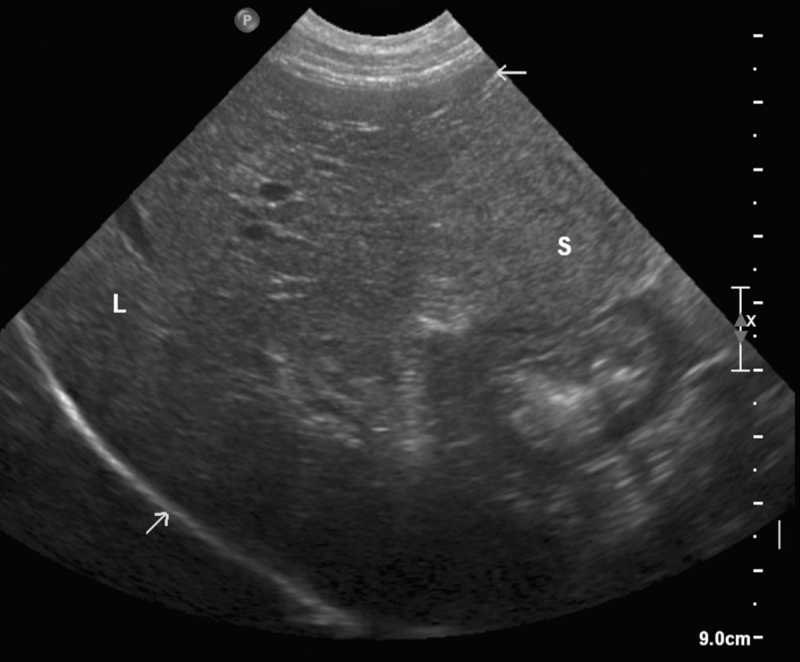

Ecografía veterinaria para animales

La ecografía veterinaria a domicilio es una técnica diagnóstica no invasiva que permite evaluar órganos internos de forma rápida y precisa. Gracias a equipos portátiles, se pueden realizar estudios abdominales, reproductivos o urinarios sin necesidad de desplazamientos.

Al realizarse en un entorno tranquilo, se reduce la necesidad de sedación y se mejora la calidad de la exploración. Además, el veterinario puede explicar los resultados al momento, facilitando la toma de decisiones clínicas.